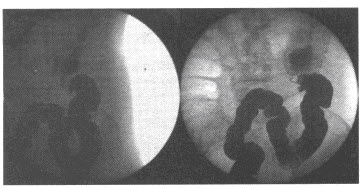

27、多项选择题

男,12岁,上腹痛1周,无规律,无黑便史。体检:剑突下有压痛,结合图像,最可能的诊断是()